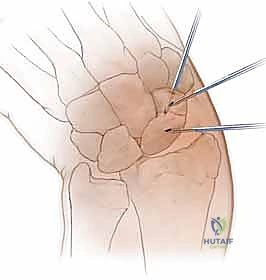

2. المدخل الظهري (Dorsal Approach): من ظهر اليد. يُعتبر الأفضل لكسور القطب القريب، حيث يوفر مساراً أسهل للوصول إلى هذا الجزء العميق بمحاذاة المحور الميكانيكي للعظم.

الخطوة 2: تحديد مسار المسمار بدقة (Guidewire Placement)

هذه هي الخطوة الأكثر أهمية والتي تتطلب مهارة استثنائية. يقوم د. هطيف بعمل شق صغير جداً (بضعة مليمترات). باستخدام جهاز الأشعة، يقوم بإدخال سلك معدني